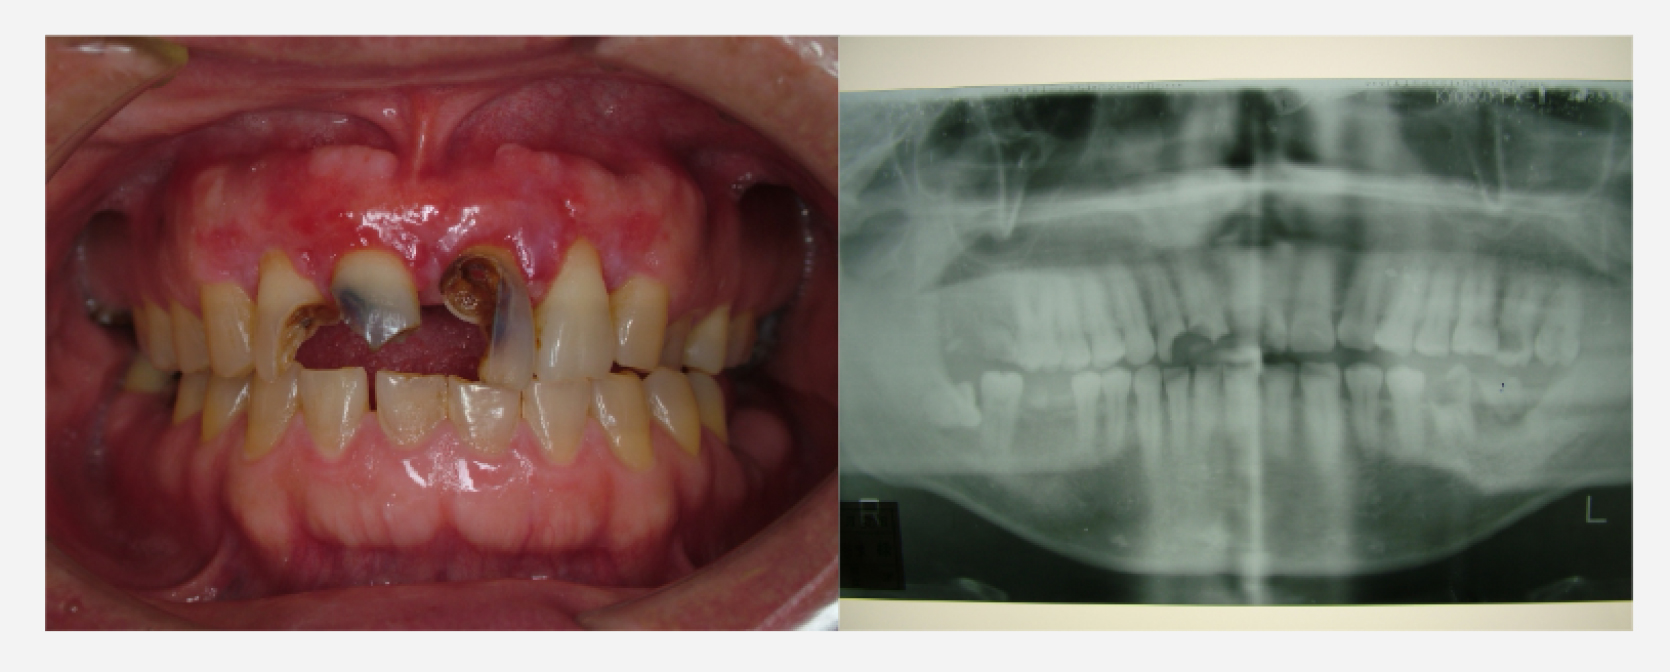

治療前

治療経過

術後3ヶ月 仮歯装着

術後1年後

治療前と治療後

| 治療内容 | 歯周外科:歯肉弁根尖側移動術 (Apically Positioned Flap Operation) |

|---|---|

| 患者様の年齢 | 35歳 |

| 患者様の性別 | 男性 |

| 治療期間 | 初診時より2年 |

| 治療回数 | 矯正治療合わせて85回程度 |

| 治療費用 | インプラント:150万円/歯周外科:3万円/補綴治療:50万円 |

| 治療で得られるメリット |

|

| 治療する際に起こる リスク・副作用 |